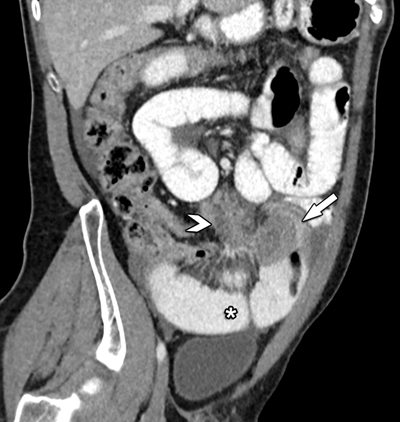

Computed tomography (CT) confirmed a large mesenteric tumoral mass extending towards the ileum, where circumferential small bowel wall invasion caused intestinal obstruction (Figures 1 and 2). There was only a moderate amount of ascites. No signs of peritoneal carcinomatosis, distant metastases or free intra-peritoneal air were present.

Figure 2

Oblique coronal view of contrast-enhanced CT shows the close relation between the mesenteric mass (arrowhead) and its extension towards the small bowel (arrow). Note the distended small bowel loops (*).